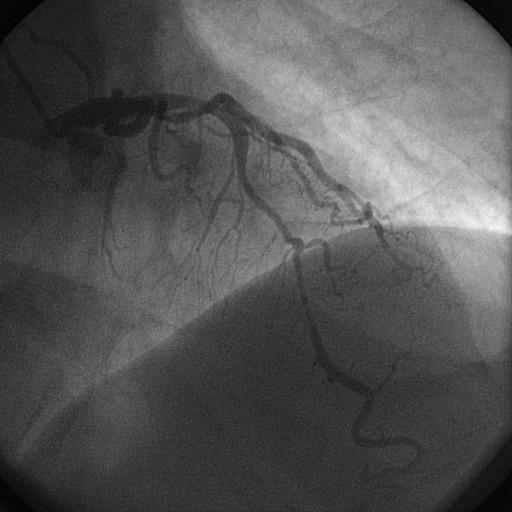

Frequentemente, quando vemos laudos de cinecoronariografias ou angioplastias coronarianas, nos deparamos com a descrição de uma artéria coronariana, seguido de “fluxo TIMI 0, 1, 2 ou 3”. Mas o que é isso? Como é feita essa graduação?